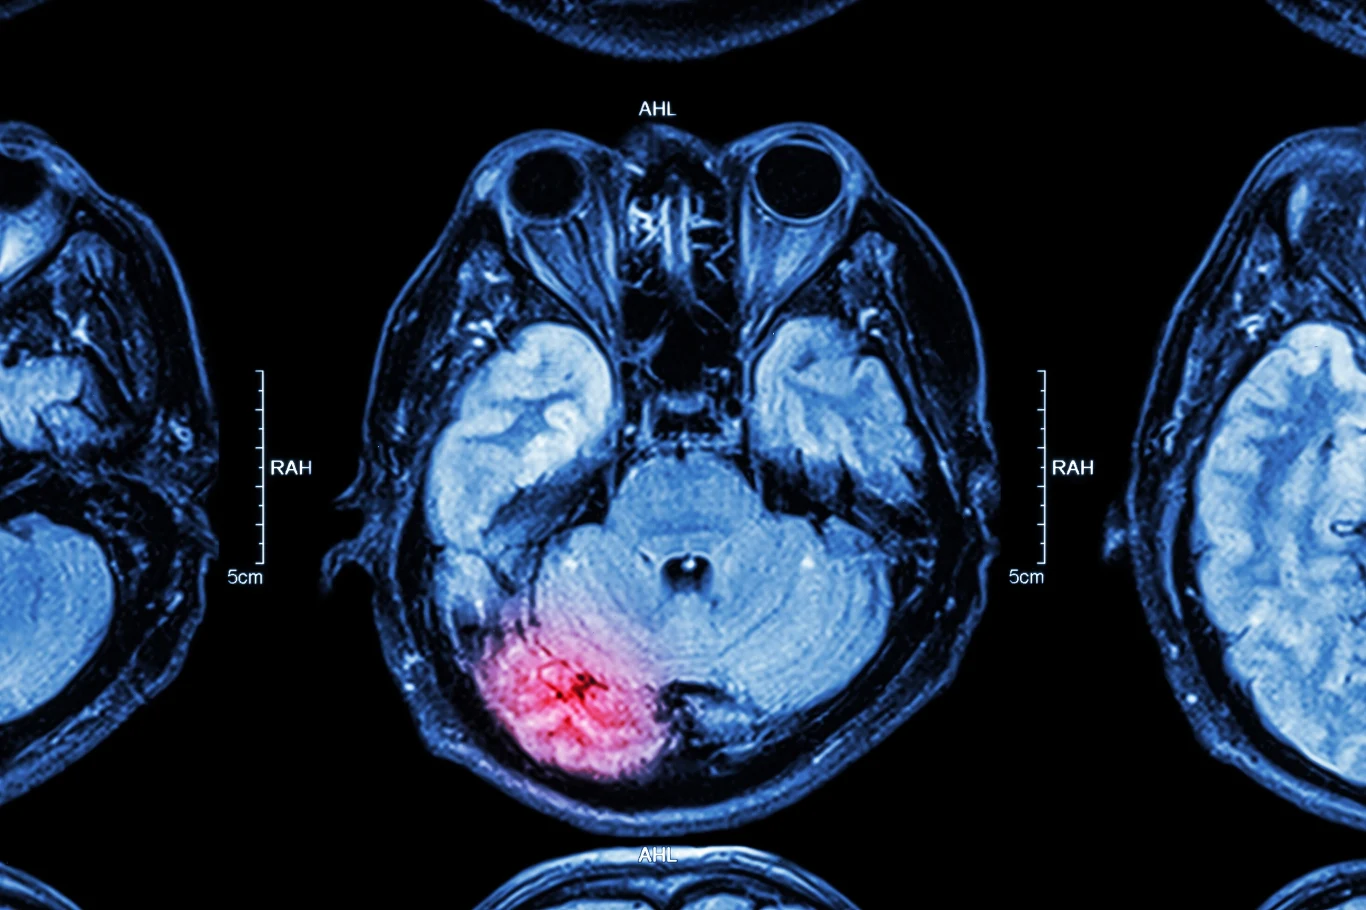

Coraz więcej dowodów sugeruje, że infekcja SARS-CoV-2 może powodować szereg zaburzeń neurologicznych. Naukowcy z University College London (UCL) opisali ponad 40 dodatkowych przypadków osób z COVID-19, które doznały tymczasowej dysfunkcji mózgu, udaru, uszkodzenia nerwów lub innych poważnych skutków neurologicznych. Co ciekawe, większość z pacjentów nie miała nawet poważnych objawów oddechowych COVID-19.

- Powinniśmy być czujni i zwracać uwagę na te powikłania u osób, które miały COVID-19. Czy zobaczymy falę uszkodzeń mózgu związanych z pandemią - podobną do epidemii encephalitis lethargica w latach 20. i 30. ubiegłego wieku po pandemii grypy z 1918 r. - nie wiemy - powiedział dr Michael Zandi, współtwórca Instytutu Neurologii UCL Queen Square.Im więcej wiemy o COVID-19, tym bardziej oczywiste staje się, że nie jest to prosta choroba układu oddechowego. Wiele zespołów naukowych z całego świata wykazało, że wirus może uszkadzać organy inne niż płuca - w tym serce, nerki, jelita, wątrobę i - jak pokazują nowe badania - mózg.W badaniu przeprowadzonym w UCL zaburzenia mózgu znaleziono u 43 osób (w wieku od 16 do 85 lat), które albo miały potwierdzoną infekcję SARS-CoV-2, albo miały podejrzenie COVID-19 podczas leczenia w szpitalu. W tej wybranej grupie zidentyfikowano 12 przypadków zapalenia mózgu, 10 przypadków tymczasowej dysfunkcji mózgu z delirium, 8 przypadków udarów, 8 innych z uszkodzeniem nerwów i pozostałe z "różnymi zaburzeniami centralnymi, które nie pasowały do żadnej kategorii".

SARS-CoV-2 nie został wykryty w płynie mózgowo-rdzeniowym żadnego z badanych pacjentów. Oznacza to, że infekcja nie zaatakowała bezpośrednio mózgu w celu wywołania choroby neurologicznej, ale być może jest wynikiem zapalenia lub innej reakcji układu odpornościowego. Jak wspomniano, naukowcy ostrzegają, że ta niewielka, ale znacząca liczba zaburzeń mózgu wywołanych przez nowego koronawirusa sugeruje, że świat może stanąć w obliczu większej "epidemii" uszkodzeń mózgu. Pandemia grypy z 1918 r., która odebrała życie od 50 do 100 milionów ludzi, została połączona z wybuchem choroby mózgu znanej jako zapalenie mózgu von Economo (śpiączkowe zapalenie mózgu). Jest zbyt wcześnie, aby przewidzieć, czy trwająca pandemia COVID-19 doprowadzi do porównywalnej fali zapalenia mózgu lub innego zaburzenia mózgu w następnym dziesięcioleciu.